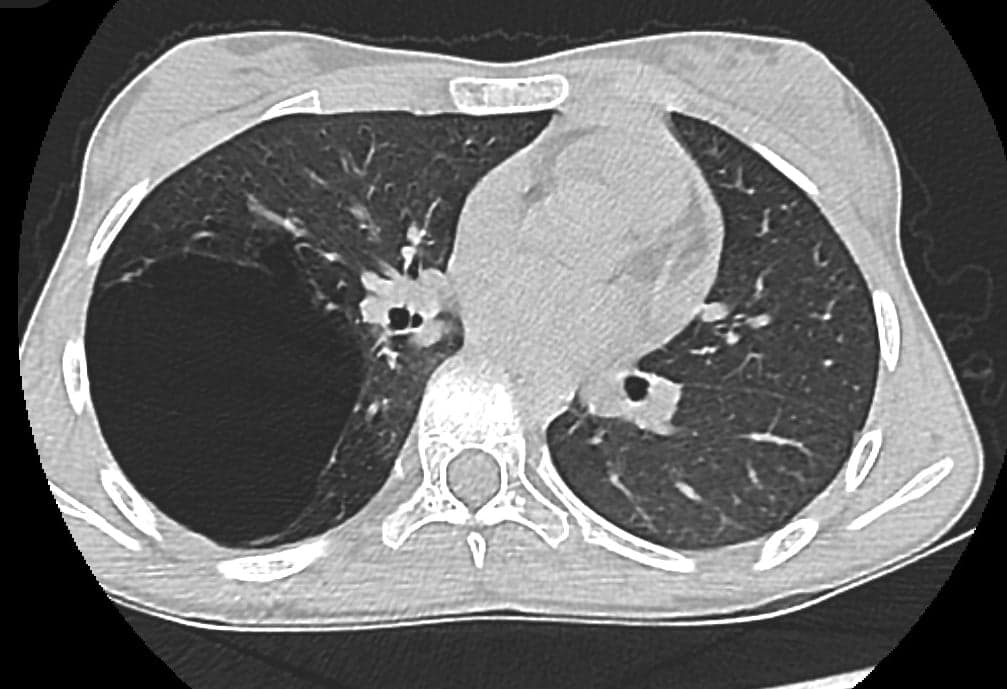

Fetita, balerina de performanta, a fost descoperita la un control de rutina solicitat pentru a continua baletul cu o modificare la examenul clinic toracic. In copilarie, a avut numeroase infectii respiratorii joase. Tomografia computerizata a aratat ca intregul lob pulmonar inferior drept era transformat in totalitate de un chist gigant, cu diametrul cel mai mare de 9.8 cm. S-a efectuat operatia de indepartare a intregului lob pulmonar – lobectomie pulmonara - printr-o singura incizie de doar 3 cm la nivelul toracelui, fara a se departa coastele, ceea ce a insemnat o agresiune mult mai mica la nivelul toracelui, comparativ cu interventia deschisa, clasica. Fetita s-a mobilizat chiar din ziua interventiei si in a 4-a zi postoperator a plecat acasa. Examenul histopatologic a evidentiat ca leziunea era un tip foarte rar de malformatie congenitala pulmonara - malformatia congenitala adenomatoida chistica (CCAM).

Tomografia computerizata toracica este o metoda rapida si sigura de evaluare a extinderii CCAM la toate categoriile de varsta. In ultimii ani, folosirea unor tehnologii imagistice avansate de tipul tomografiei computerizate de rezolutie inalta (HRCT) si a softurilor de post-procesare a permis un diagnostic din ce in ce mai acurat.